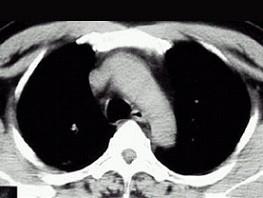

问题 21岁,近2个月来咳嗽,痰中带血丝,午后手心足底发热,盗汗、心悸,胸部CT见图,最可能的诊断是 ( )

选项 A、右上肺炎 B、肺囊肿 C、继发性肺结核空洞形成 D、右肺脓肿 E、右上肺癌性空洞形成

答案 C